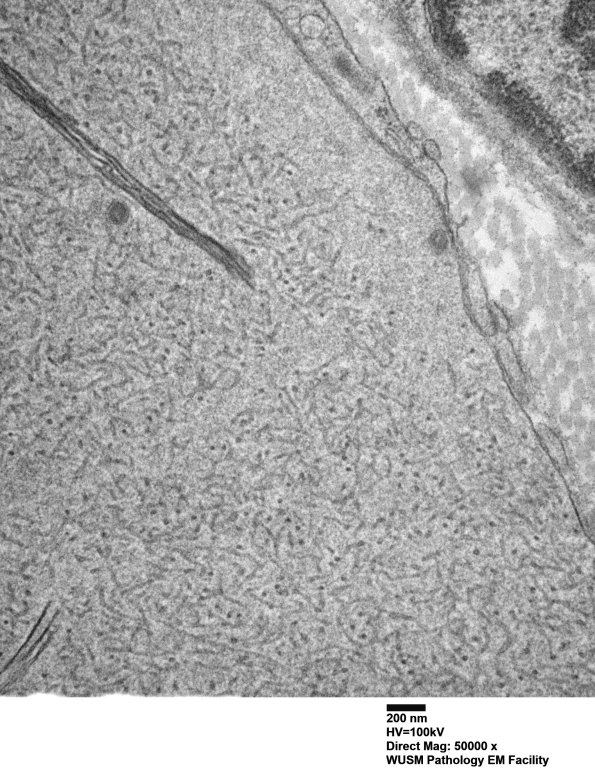

In these images delicate uncompacted tubulovesicular elements, dense axoplasm and a membranous cleft are illustrated. (electron micrographs)